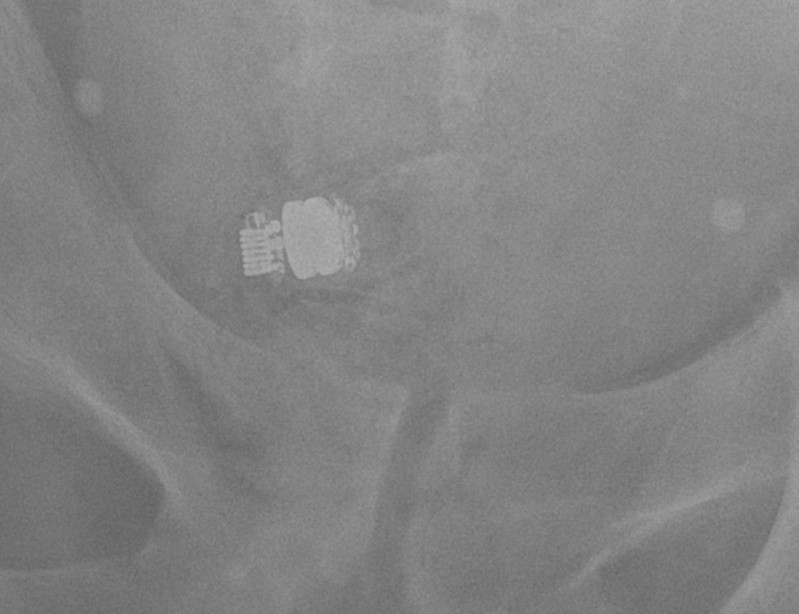

Video Capsule Endoscopy Radiology . Video capsule endoscopy (vce) is a powerful diagnostic tool that has proved especially useful in imaging the small intestine. This book is simultaneously a superb atlas and a detailed guide to all aspects of video capsule endoscopy. History, technique, performance, reading, indications, contraindications, outcomes,. Video capsule endoscopy (ce) provides a noninvasive option to assess the small intestine, but its use with respect to endoscopic. Frontal abdominal radiograph reveals two endoscopic video capsules in right lower quadrant. Wireless video endoscopy or video capsule endoscopy (vce) is a noninvasive technology designed primarily to provide. Photograph shows wireless video capsule (m2a capsule, given imaging).

Image Video Capsule Endoscopy Radiology Frontal abdominal radiograph reveals two endoscopic video capsules in right lower quadrant. Video capsule endoscopy (vce) is a powerful diagnostic tool that has proved especially useful in imaging the small intestine. This book is simultaneously a superb atlas and a detailed guide to all aspects of video capsule endoscopy. Photograph shows wireless video capsule (m2a capsule, given imaging). Wireless video. Video Capsule Endoscopy Radiology.